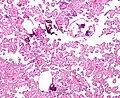

Histopathology

The tumor is neuroectodermal in origin and similar in structure to a normal choroid plexus. They may be created by epithelial cells of the choroid plexus. Papillary fronds lined by bland columnar epithelium are visible under the microscope. Normal absences include mitotic activity, nuclear pleomorphism, and necrosis.[10] Tumors have positive immunohistochemistry for cytokeratin, vimentin, podoplanin, and S-100.[11] Up to 20% of choroid plexus papilloma patients may test positive for glial fibrillary acidic protein (GFAP).[12] Studies have found that fourth ventricle cancers express more S100 than lateral ventricle tumors, and older patients (over 20 years) express more GFAP and transthyretin than younger patients.[13] Some individuals with choroid plexus papilloma have germline TP53 gene mutations, according to genetic analyses.[14] These cancers rarely exhibit nuclear p53 protein positivity. Aicardi syndrome, hypomelanosis of Ito, and 9p duplication are syndromic correlations of choroid plexus papilloma.